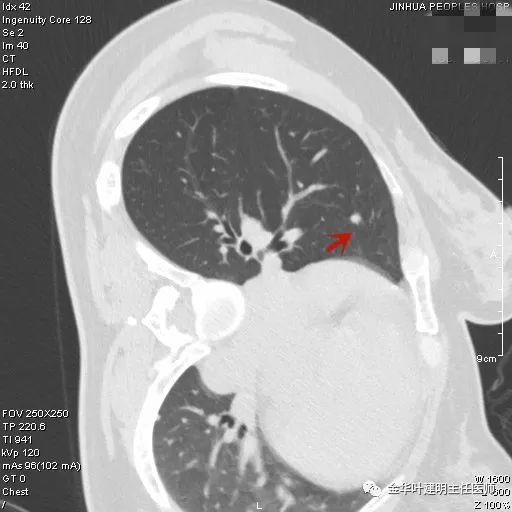

上图是纤维增生,但我们看病灶有明显的叶间胸膜牵拉,虽然力度弱,但这么小的病灶能指望它有多少力度呢?恶性还是不能除外的。